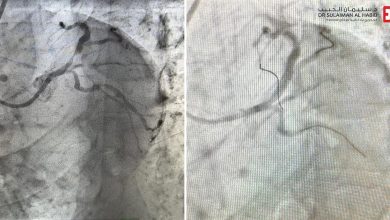

مستشفى الدكتور سليمان الحبيب بالمحمدية في جدة يُنقذ مراجع مصاب بانسداد حاد نسبته “99%” بالشريان التاجي الأيسر

بفضل من الله – أنقذ مستشفى الدكتور سليمان الحبيب بالمحمدية في جدة، حياة رجل عمره “65” عاماً، ويعاني من جلطة…